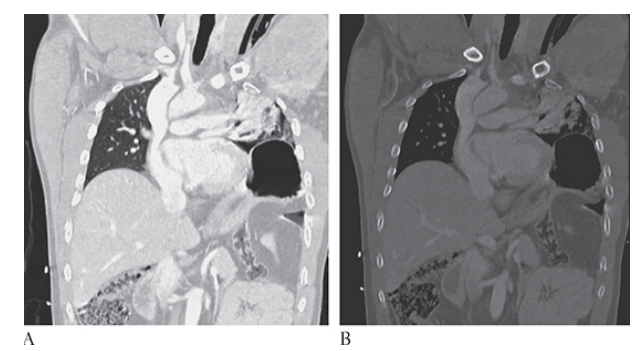

What is A

Superior Vena Cava Syndrome. CECT coronal and MPR CECT sagittal

What is B

Superior Vena Cava Syndrome. CECT coronal images show significant narrowing of the superior vena cava with development of multiple collaterals.

Superior Vena Cava Syndrome. Axial CECT shows significant narrowing of the superior vena cava with development of multiple collaterals.